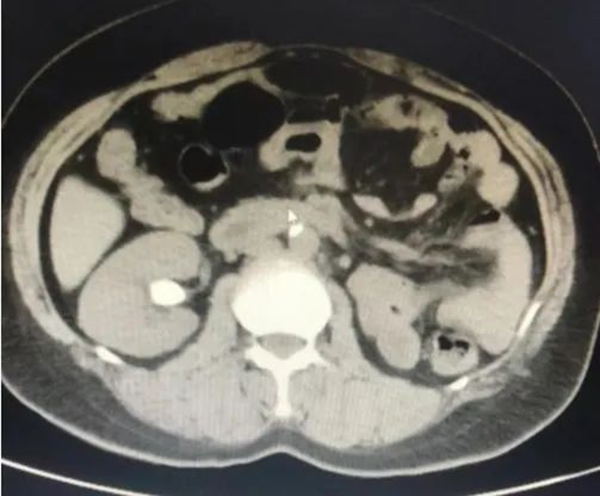

萬(wàn)般絕望之際,王女士多方打聽(tīng),在朋友的推薦下來(lái)到徐州市中醫(yī)院泌尿外科就診。入院后,經(jīng)CT檢查顯示,王女士右腎下盞結(jié)石,直徑為2.1*1.6cm,結(jié)石CT值1360Hu,初步判斷為草酸鈣結(jié)石。

右腎結(jié)石(術(shù)前)